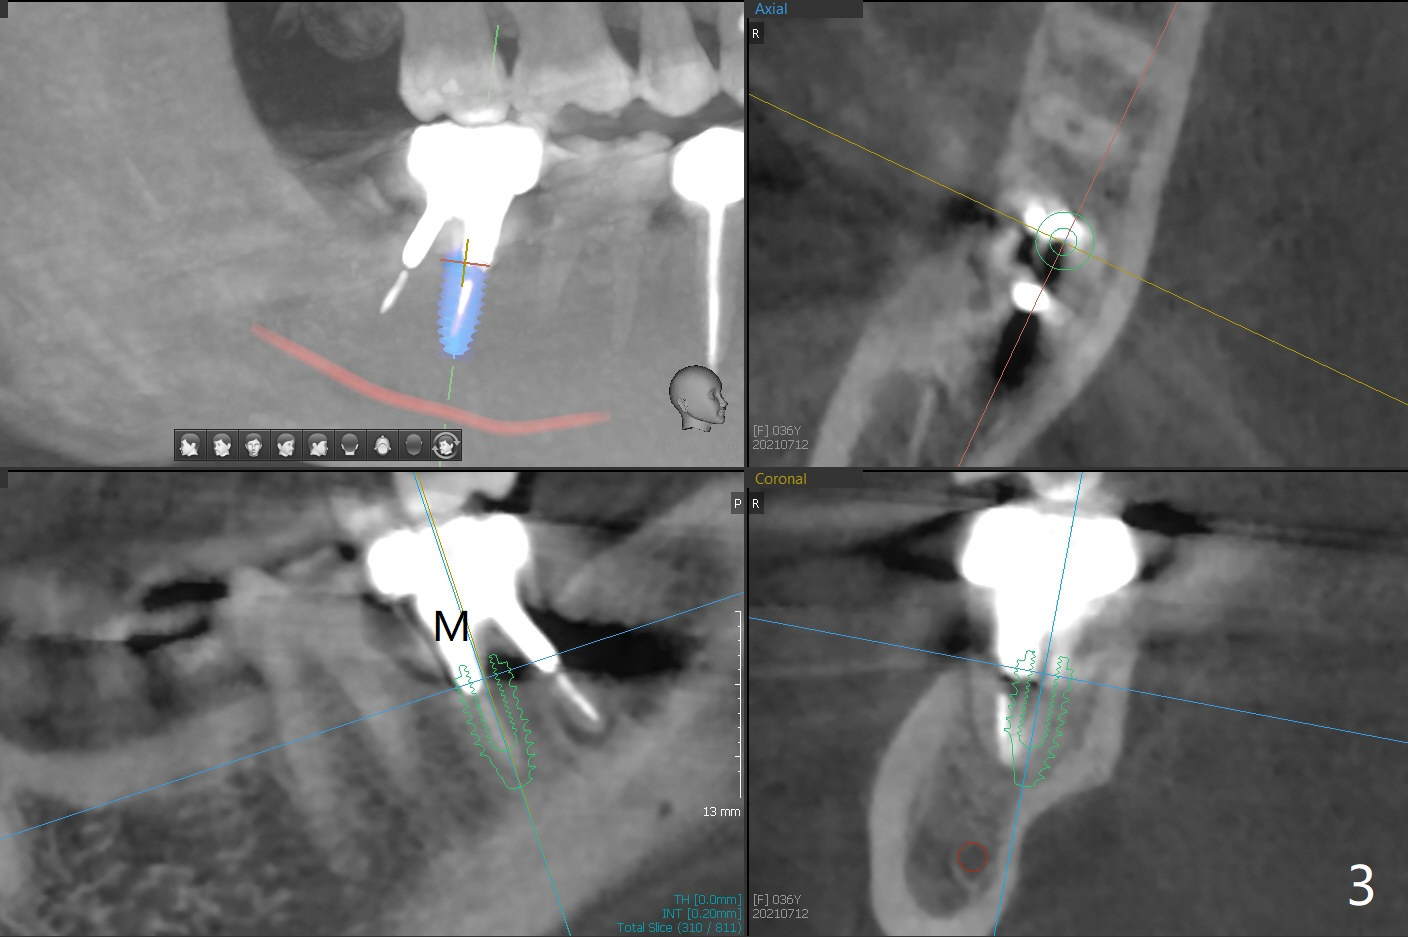

More Bone When Implant Placed in Mesial Socket

A 36-year-old woman has had an abscess and bone loss associated with the tooth #31 (Fig.1). It appears that there is less bone to support an implant when it is placed in the septum (Fig.2 S) than in the mesial socket (Fig.3 M).